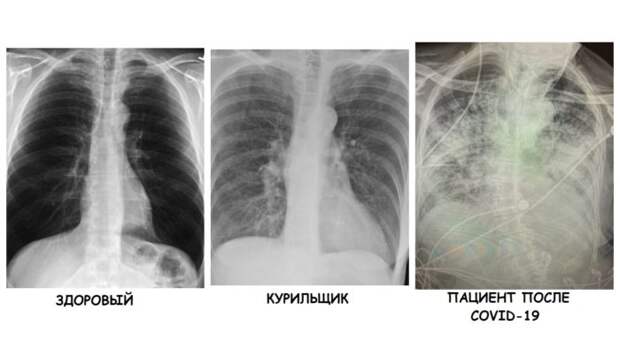

Рентген здоровых легких: примеры снимков и советы

Раздел: Сокровищница опыта